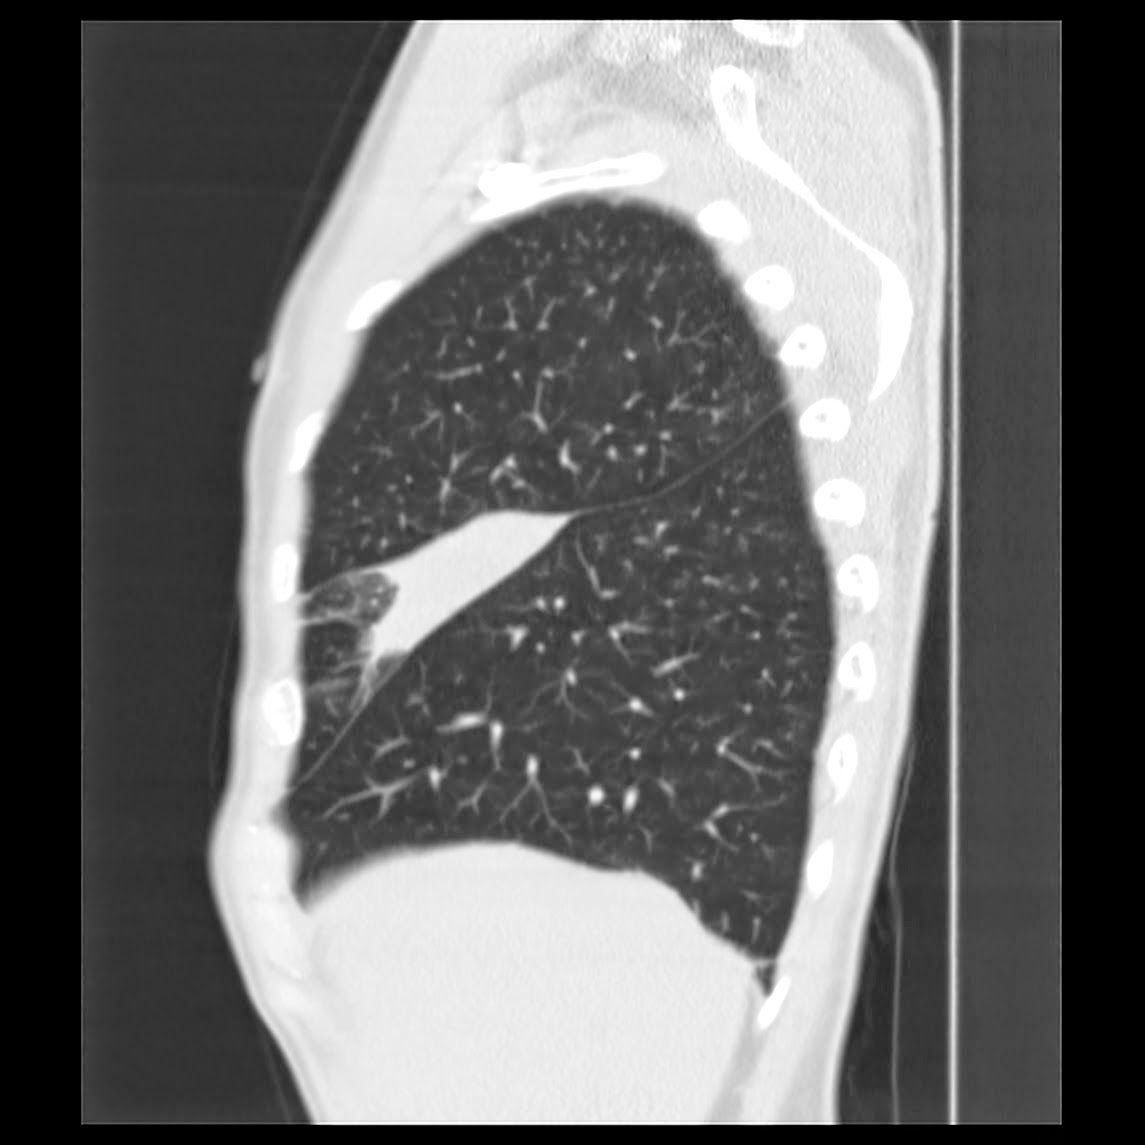

Caso interesante #6

Otro casito de un tórax para localizar la consolidación

Segmento lateral del lóbulo medio